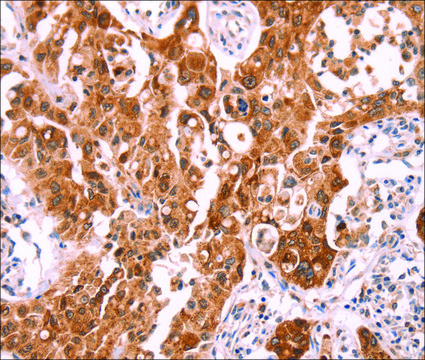

Anti-NCEH1 antibody produced in rabbit

Anti-AADACL1, Anti-KIAA1363, Anti-NCEH, Anti-NCEH1, Anti-neutral cholesterol ester hydrolase 1